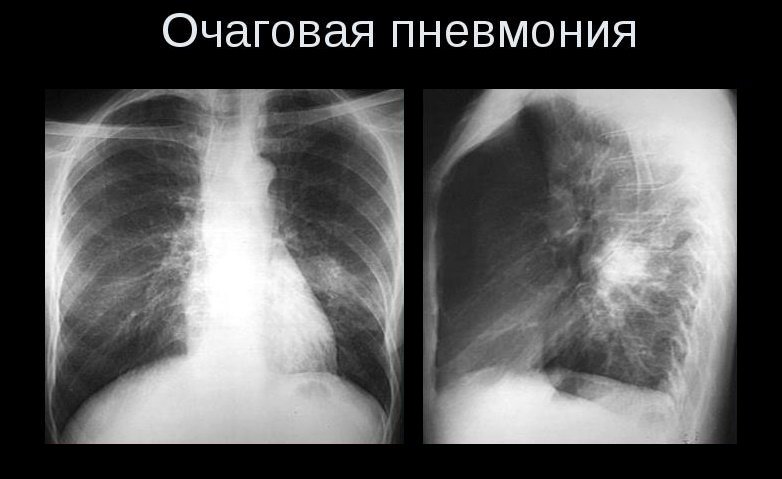

Очаговая пневмония

Ее диагностировать трудно, особенно на ранних этапах. При очаговой пневмонии уплотнения небольшие и называются они инфильтратами (всегда приводят к увеличению и расширению корня легких). В первые дни болезни инфильтраты могут и не определяться, но вскоре на их месте появляется воспалительный очаг уплотнения.

- Очаговая форма. На рентгене отображаются небольшие (1-1,5 см) тени со слабой или умеренной интенсивностью окраски, неоднородной структурой и нечеткими границами. Очаги поражения могут быть единичными или множественными, а в некоторых случаях они сливаются в одно большое пятно. Корни легких расширены, причем нарушения нормального рисунка органа могут сохраняться в течение нескольких дней после выздоровления.

ВАЖНО! Сложнее всего поддается диагностике очаговая пневмония – на первых стадиях она проявляется небольшими очагами инфильтрации, которые не всегда заметны на рентгене.